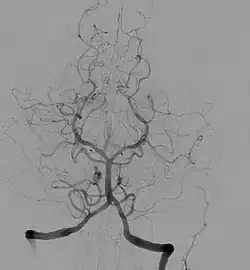

Angiogram showing a transverse projection of the vertebro basilar and posterior cerebral circulation

Angiography is the use of fluoroscopy to view the cardiovascular system. An iodine-based contrast is injected into the bloodstream and watched as it travels around. Since liquid blood and the vessels are not very dense, a contrast with high density (like the large iodine atoms) is used to view the vessels under X-ray. Angiography is used to find aneurysms, leaks, blockages (thromboses), new vessel growth, and placement of catheters and stents. Balloon angioplasty is often done with angiography.